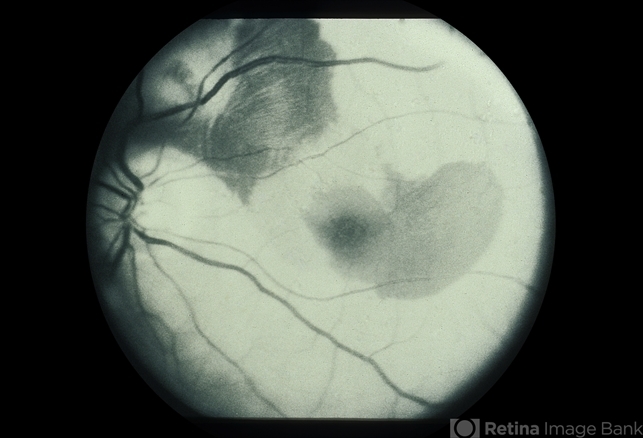

Peripapillary CNVM - ARMD

Peripapillary CNVM - ARMD, 81-old-year female.